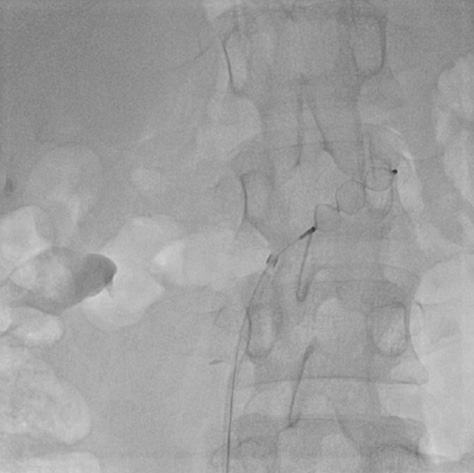

We decided to submit the patient to a cardiac catheterization study. We found a telediastolic, single ventricular pressure of 11 mm Hg. The mean pressure within the Fontan circulation was 23 mm Hg and there was a moderate stenosis across the left pulmonary artery with a peak-to-peak systolic pressure gradient of 4 mm Hg (Figure 1). At that stage, a CP covered stent (B. Braun Interventional Systems, Inc.; 45 mm, 8 zig configuration) was implanted over a 12- X 50-mm BIB balloon (B. Braun Interventional Systems, Inc.), which was then implanted across the left pulmonary artery. The pressure gradient was eliminated and the mean pressure in the Fontan circulation was 19 mm Hg.

Figure 1. Angiography in the Fontan circuit in the anteroposterior view. The left pulmonary artery is moderately hypoplastic.